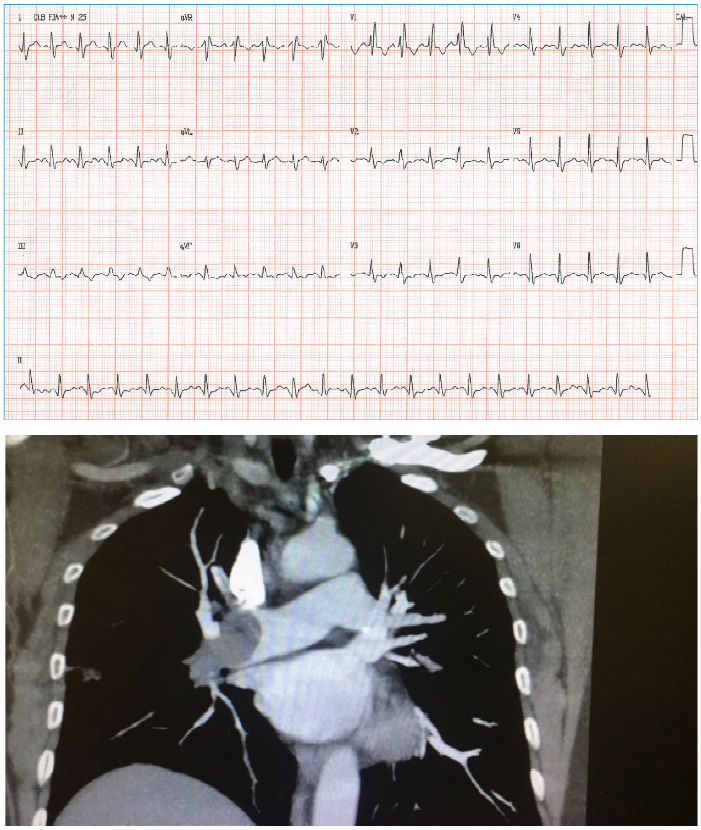

Edileuza, 64 anos, tabagista e diabética, procura serviço de pronto atendimento com dor precordial há 2 horas e PA = 149x96 mmHg. A paciente realiza eletrocardiograma, conforme imagem a seguir:

Após a realização do eletrocardiograma, o plantonista institui algumas condutas terapêuticas. Porém, após a utilização de uma das medicações, o quadro de Edileuza evolui para hipotensão acentuada, mal-estar generalizado e sintomas de baixo débito, sem rash cutâneo ou angioedema. Qual medicação poderia justificar o quadro dessa paciente?

Sr. JG, 60 anos, procura o serviço hospitalar com falta de ar e dor torácica iniciada há 40 minutos. Referiu que, na véspera, começou a se sentir mal e esteve no mesmo hospital, quando foi examinado e realizou radiografia de tórax e eletrocardiograma. Na ocasião, os médicos lhe disseram que não encontraram anormalidades relevantes e deram alta a ele, que foi para casa. O paciente possui histórico de tabagismo crônico. Exame físico: FC = 134 bpm, FR+ 36irpm, PA = 89x58 mmHg, Oximetria = 85%, sudorético. AR = murmúrio vesicular fisiológico, sem ruídos adventícios; ACV: bulhas rítmicas e fonéticas. Seguem abaixo as imagens do ECG e TC de tórax.

Qual a conduta CORRETA para esse paciente?